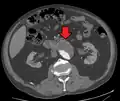

A ruptured AAA with an open arrow marking the aneurysm and the closed arrow marking the free blood in the abdomen -

An axial contrast-enhanced CT scan demonstrating an abdominal aortic aneurysm of 4.8 by 3.8 cm -